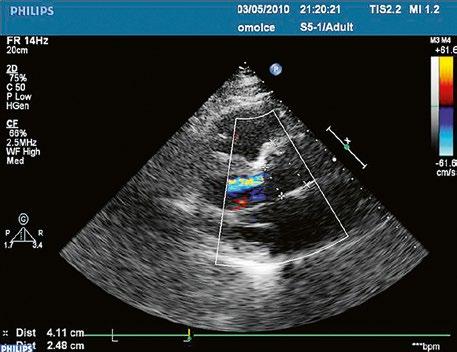

Supravalvární pulmonální stenóza a stenózy větví plicnice bývají součástí komplexních VSV (např. Fallotovy tetralogie) nebo syndromů (Williamsův syndrom, syndrom Noonanové, syndrom vrozené rubeoly, Alagillův syndrom aj.) (Obr. 45.39). Získané stenózy větví plicnice, ale i úplný uzávěr větve plicnice můžeme vidět po spojkových operacích podle BlalockaTaussigové (Obr. 45.40, Obr. 45.41). Pro zobrazení supravalvárních a periferních stenóz plicnice je optimální CT angiografie (Obr. 45.40, Obr. 45.41, Obr. 45.42, Obr. 45.43).

Obr. 45.40 CT angiografie, 8mm stenóza a deformace levé větve plicnice (šipka) po spojkové operaci podle BlalockaTaussigové v dětství LPA – levá větev plicnice, PA – kmen plicnice, RPA – pravá větev plicnice

Obr. 45.42 CT angiografie. Dilatace kmene plicnice (PA), periferní stenóza v oblasti bifurkace a odstupu pravé větve plicnice (RPA) označena šipkou, odstup levé větve plicnice (LPA) je také lehce zúžen.

Obr. 45.41 Uzávěr levé větve plicnice jako následek provedené spojky podle BlalockaTaussigové v dětství, CT angiografie

Obr. 45.43 CT angiografie, šipkou označena významná odstupová stenóza levé větve plicnice (LPA), lehčí stenóza odstupu pravé větve plicnice (RPA), kalcifikace v oblasti pulmonální chlopně

Pro zobrazení plicnice a jejích větví je nejvhodnější CT angiografie (Obr. 45.40, Obr. 45.41, Obr. 45.42, Obr. 45.43). Magnetická rezonance zhodnotí velikost a funkci pravé komory i regurgitační frakci u pulmonální regurgitace (Video 45.41).